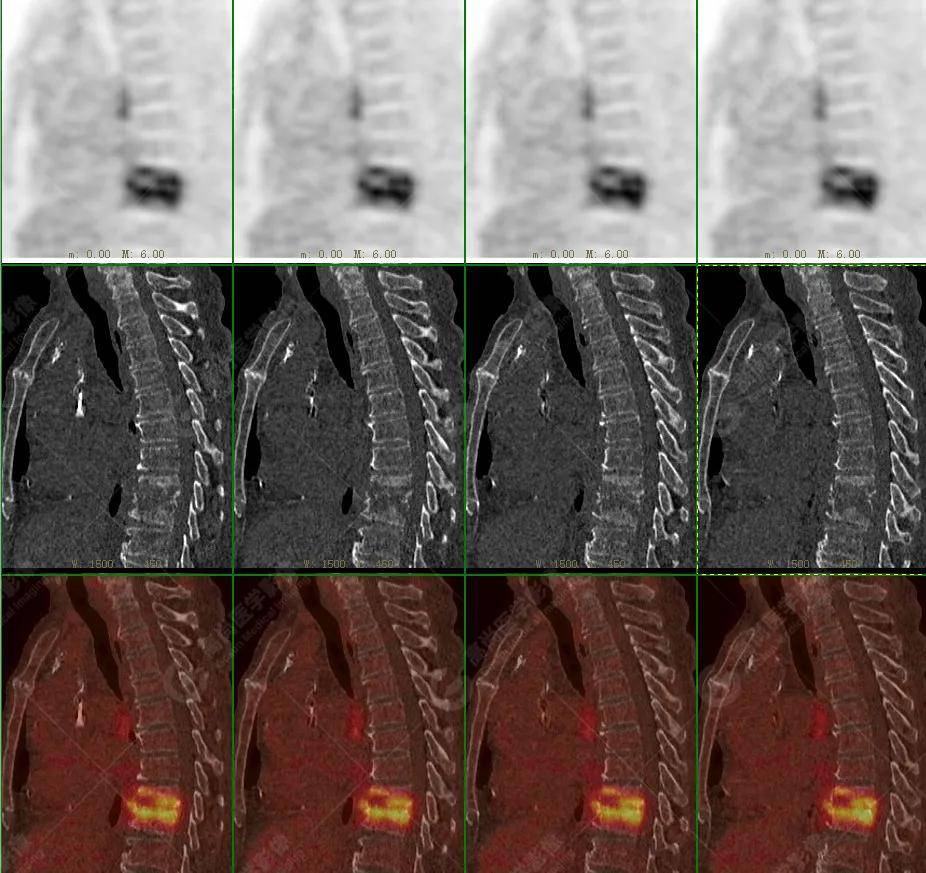

【高尚病例】18f-fdg pet/ct显像应用于骨结核

图片尺寸916x838